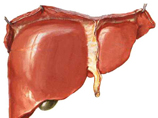

Чтобы понять, что такое желчнокаменная болезнь, обратимся к анатомии. В печени вырабатывается желчь – жидкость желтовато-зеленого цвета, участвующая в процессе пищеварении. Под печенью расположен...